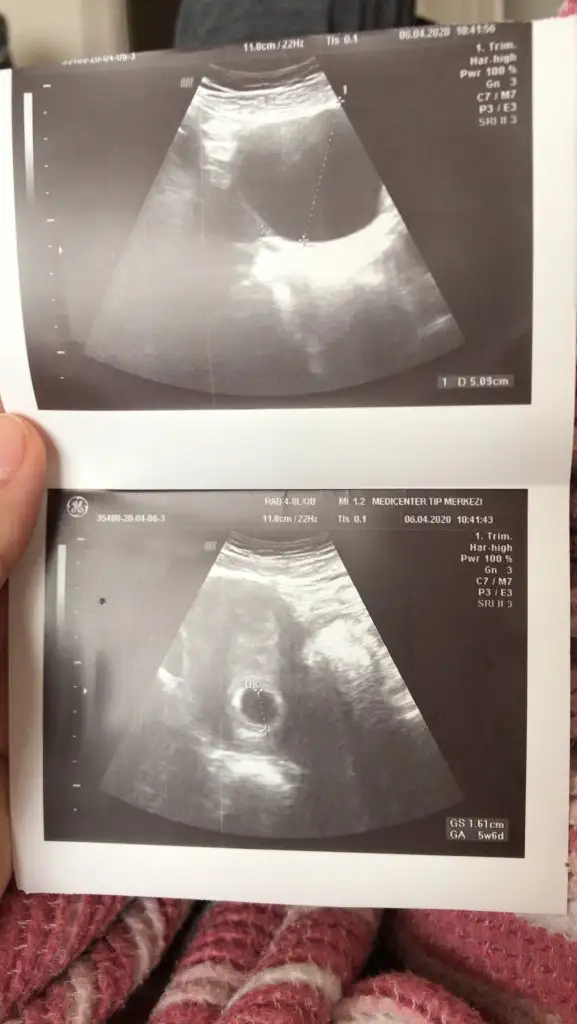

Kızlar az önce doktora gittim 7 haftalık hamileyim ama virüsten dolayı bakmadı doktor doğru düzgün kese var kistin var deyip hemen çık bu kadar dedi kalp atışı için 3 hafta sonra gel dedi hiç bişey anlamdım yaa anlayan varsa yardımcı olabilir mi

7 haftalik degil asagida 5+3yaziyor yani 8.haftada gel demis kalp atisi icin cnm

Canım kese görünmüş ama bebek yok hala 5+6 görünüyorsun ultrasona göre inşallah kalp atışınıda duyarsın ilerde. Kist için ilaç falan vermedimi.

Kızlar ilk muayenemdi bu kağıdı verdi yolladı şimdi farlettim bende 5 hafta 6 günlükmüş ultrosana göre kist için hamileliğin ileri zamanları geçer dedi sadece o kadar